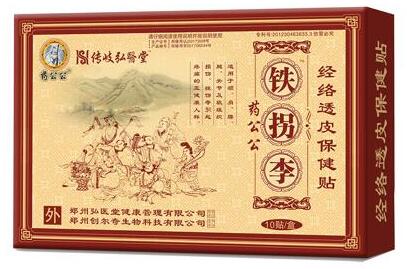

传岐弘医堂【铁拐李经络透皮保健贴】是由二十多种中药材精华萃取成膏,直接贴敷于皮肤患处,可有效渗透皮肤表层直达病灶处,消除病灶内的无菌性炎症及水肿,膏体中的中药成分渗入病灶可很好的修复受损的椎体,激活病灶处细胞功能,恢复细胞正常代谢能力,使身体逐渐恢复到正常的状态。用过的腰椎病患者基本都已康复,反馈良好,可以放心使用。

了解产品详情可进入【铁拐李经络透皮保健贴】官方网站http://vipp.vemi123.com在线咨询/自助下单或进入淘宝店铺http://gy120.taobao.com即可在线订购。